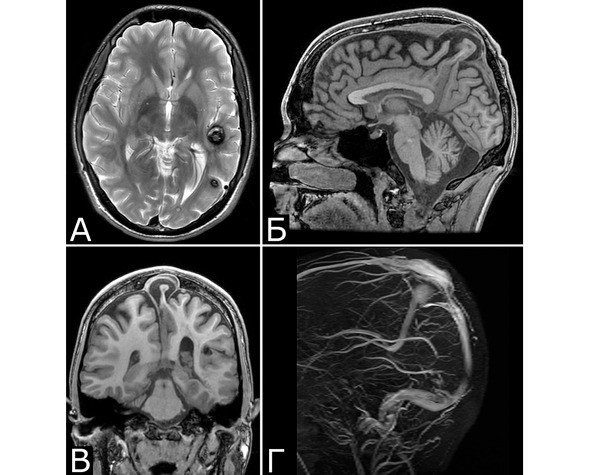

Сочетание каверномы с АВМ выявлено у двух больных, причем в обоих случаях клинические проявления заболевания были обусловлены АВМ, а кавернома явилась случайной находкой (рис. 1).

У 6 больных каверномы сочетались с венозными ангиомами и аномалиями венозной системы. Крупные патологические вены, расположенные в непосредственной близости к КМ, часто обнаруживают при МРТ или на операции, в связи с чем многие авторы рассматривают их как единую патологию (28, 93, 154, 351, 357). Тем не менее, в ряде случаев кавернозные и венозные мальформации можно четко дифференцировать как самостоятельные образования, особенно если они находятся в разных отделах мозга. У двух больных патология венозной системы представляла собой аномалию сразу нескольких крупных венозных коллекторов головного мозга (рис. 2).

Рис. 1.Б-ная Г., 27 лет. Сочетанная сосудистая патология мозга: КМ передне-медиальных отделов височной доли справа (А – МРТ, режим Т1; Б – МРТ, режим Т2); АВМ медиальных отделов лобно-теменной области справа (В – МРТ, режим Т2;Г – МРТ-АГ). Клиническое течение: редкие вторично-генерализованные судорожные эпилептические припадки, начинающиеся с судорог в левых конечностях

Рис. 2.Б-ной П, 22 г. Сочетанная сосудистая патология мозга: Множественные КМ головного мозга. Аномалия развития венозной системы мозга. А – КМ височной, теменной и затылочной долей слева (МРТ, режим Т2, аксиальная проекция). Б, В – аномалия развития костей и оболочек мозга в виде локальной деформации внутренней костной пластинки и губчатого вещества теменных костей в области впадения патологической вены в ВСС. Расщепление аномального ВСС на две лакуны, пролабирование мозга в область дефекта (МРТ, режим Т1, сагиттальная и фронтальная проекции). Г – аномалия венозной системы в виде отсутствия прямого синуса, формирования крупной патологической вены, впадающей в заднюю треть ВСС (МРТ-АГ, сагиттальная проекция)